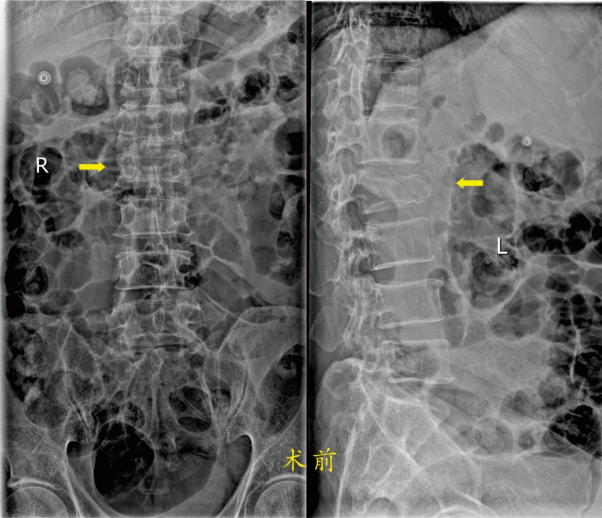

患者2:龚某某,男,67岁,因“摔伤致腰部疼痛伴活动障碍1小时余”急诊以“腰2椎体骨折”收入骨科住院。入院诊断:1.腰椎骨折(腰2);2、慢性阻塞性肺病伴有急性加重;3、肺气肿合并肺大泡;4、腔隙性脑梗死;5、.高血压病2级(高危);6、左侧颈内动脉斑块;7、高脂血症;8、肝功能不全;9、高尿酸血症;10、右肾囊肿;11、前列腺钙化灶。 骨科医师经检查及评估后了解到患者既往有高血压病,同时患有慢性阻塞性肺病,常年使用吸入药物治疗,在不吸氧时的血氧饱和度维持在90%左右,偶尔有胸闷气闭的感觉。

胸腰椎骨折的病人,术前需绝对卧床休息,长时间卧床的病人有坠积性肺炎的并发症风险,年龄越大风险越高。骨科医师向患者及家属讲解病情和治疗方法(微创手术或保守治疗即卧床休息)后,经过骨科团队讨论研究,决定为两位患者同样实施微创手术治疗:经皮穿刺椎体成形术。经过术前制定全面的手术方案,在手术室的全力配合下均顺利完成了手术。